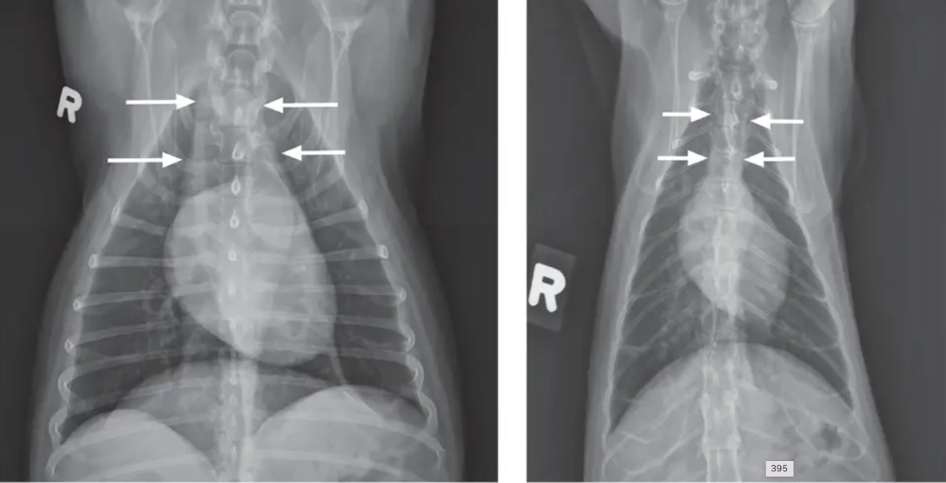

![]() | Pleural effusion - 물이 차서 심장이 안 보이고 폐가 들려 있고 끝이 뭉툭. - tracheal elevation - 흉수 뽑고 다시 찍어봐야 함. |

![]() | Pneumothorax - 폐가 쪼그라들면서 하얗게 보임 - 심장이 떠 있음 |